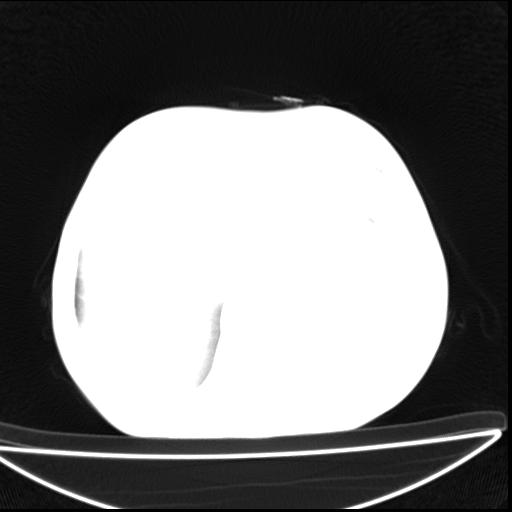

标题: CT27010:男 70岁 左胸廓塌陷,肺TB [打印本页]

男  70岁,发烧咳嗽4天。盗汗,消瘦。无痰中带血丝,以前有肺tb病史,ct见,双肺tb,左侧胸廓塌陷,左胸膜肥厚粘连。纵隔移位,右侧胸腔积液,大家说说那个心影前左肺舌叶除了肺大炮还有炎症还是干酪性肺炎?有占位吗?我看纵隔淋巴结也大。